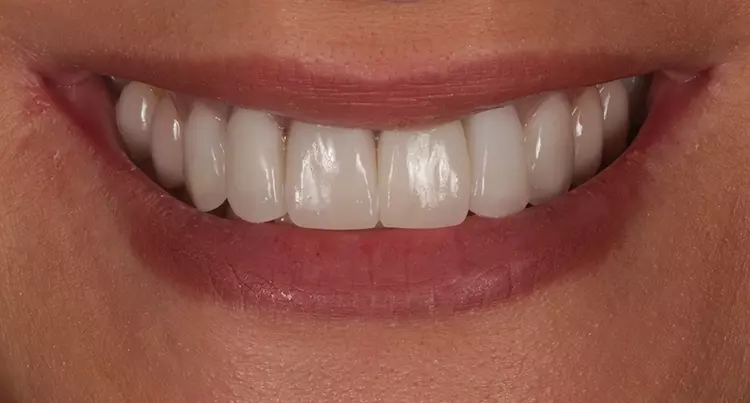

Im Oberkiefer fand die abschließende Präparation (nach Hart- und Weichgewebeaugmentation regio 22 und temporärer Versorgung mit LZP für 12 Monate) für die definitive Versorgung der Front 13 bis 23 mit Vollkeramikrestaurationen (Presskeramikgerüste „Creapress“, KLEMA, vollverblendet mit Feldspatkeramik Creation CC, KLEMA) statt (Abb. 13 und 14). In den Folgesitzungen schlossen sich die Abdrucknahme, Zentrikbissnahme, Gesichtsbogenübertragung, Anproben und definitive Eingliederung an.

Aufgrund der klinischen Beschwerdefreiheit und auch der Tatsache, dass Heilungs- und Umbauvorgänge im Gelenk noch stattfinden können, soll vorerst noch 6 bis12 Monate bei regelmäßiger klinischer Nachkontrolle abgewartet werden. Die Patientin ist subjektiv beschwerdefrei (keine Anzeichen einer Dekompensation in der klinischen Funktionsanalyse). Zudem äußert sie keine Druckdolenz der Kaumuskulatur und/oder der Gelenke [22,23] (Abb. 19 bis 22).